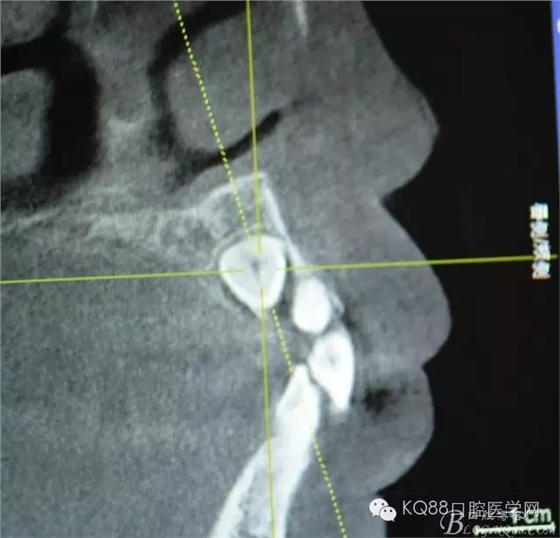

图4.纵剖面显示23位于腭侧